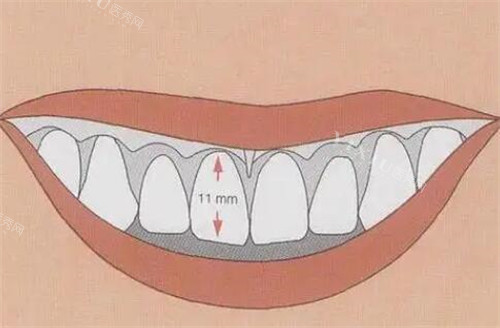

龈笑露龈,简单来说,就是在微笑时牙龈暴露过多。其成因较为复杂,一方面可能是牙齿本身发育异常,比如牙齿过短,导致微笑时牙龈比例失调;另一方面,也可能是牙龈组织过度增生,使得在正常微笑幅度下,牙龈过多地展露出来。

牙冠延长术是解决龈笑露龈问题的关键一步。它就像是技艺娴熟的雕刻师,通过手术的方式,比较准地去除部分牙龈组织和骨组织,从而暴露出更多的牙冠结构。

与牙冠延长术相结合,贴面修复能够较好地掩盖手术后的痕迹,让牙齿呈现出自然、协调的美感。无论是静态还是动态的微笑,都能展现出较好的笑容曲线,干净解决龈笑露龈的问题。